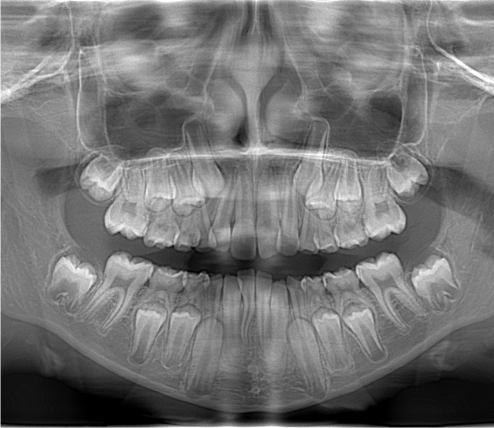

Панорамна томографія (ортопантомографія)

Метод дослідження, що забезпечує візуалізацію елементів зубощелепного апарату за допомогою спеціального пристрою – ортопантомографа. Метод дає загальну інформацію про стан зубів та кісткової тканини щелеп з відносно мінімальним променевим навантаженням. Проте в багатьох випадках проєкційні накладання та спотворення зменшують достовірність отриманої інформації та ускладнюють аналіз зображення.